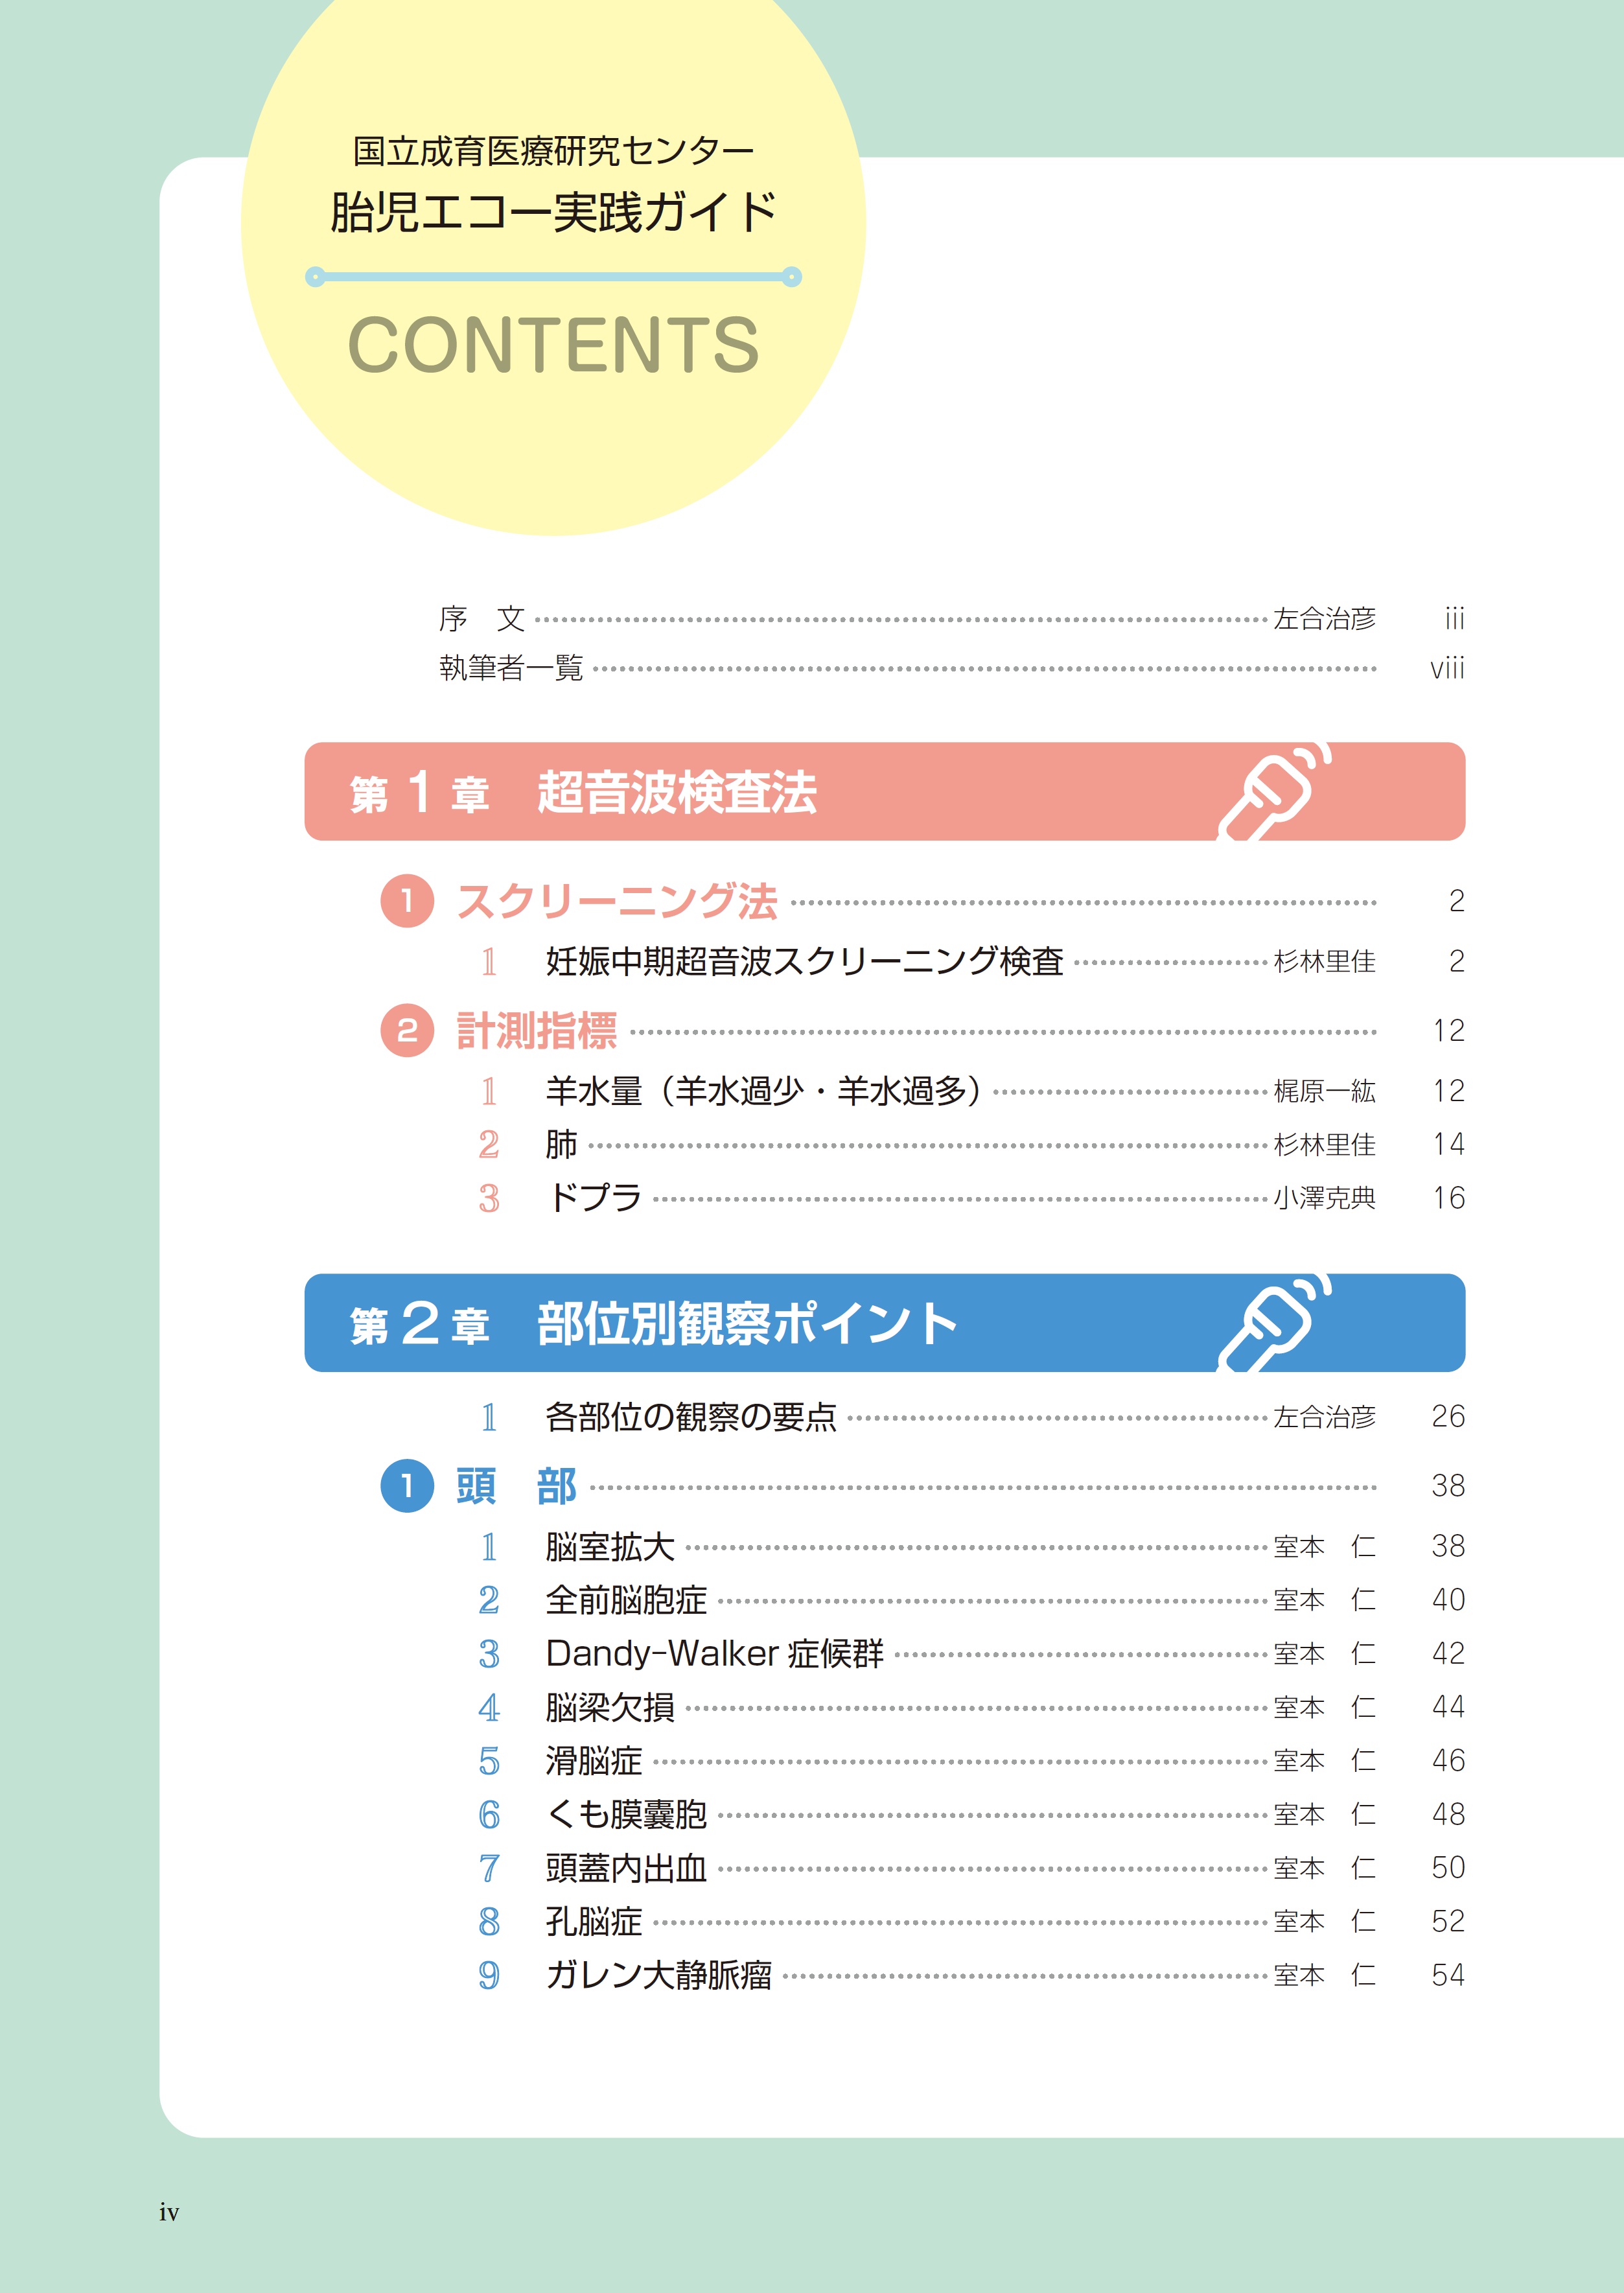

小児科学 小児整形外科テキスト 改訂第2版【電子版】 | 医書.jpの詳細情報

小児整形外科テキスト 改訂第2版【電子版】 | 医書.jp。胎児エコー実践ガイド | 診断と治療社。院内紹介|京都市北区(上京区)小児科 はったこどもクリニック。不要になったので出品します。数行ですがマーカーが引いてあります。。前橋市上大島町の小児科 医療法人しのはら小児科|予防接種。P450の分子生物学